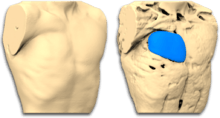

The complete or partial absence of the pectoralis muscle, is the malformation that defines Poland Syndrome. It can be treated by the insertion of a custom implant designed by CAD (computer aided design).[8] A 3D reconstruction of the patient's chest is performed from a medical scanner, to design a virtual implant perfectly adapted to the anatomy of each one.[9] The implant is made of medical silicone unbreakable rubber.

The Poland syndrome malformations being morphological, correction by custom implant is a first-line treatment.[10] This technique allows a wide variety of patients to be treated with good outcomes. Poland Syndrome can be associated with bones, subcutaneous and mammary atrophy: if the first, as for pectus excavatum, is successfully corrected by a custom implant, the others can require surgical intervention such as lipofilling or silicone breast implant, in a second operation.

The surgery takes place under general anaesthesia and lasts less than 1 hour. The surgeon prepares the locus to the size of the implant after performing a 8-cm axillary incision and inserts the implant beneath the skin. The closure is made in 2 planes.

The implant will replace the pectoralis major muscle, thus enabling the thorax to be symmetrical and, in women, the breast as well. If necessary, especially in the case of women, a second operation will complement the result by the implantation of a breast implant and / or lipofilling .